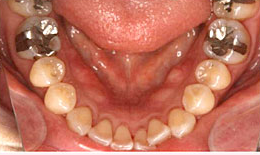

治療前

治療方法

上顎

保存困難な歯を抜歯後、インプラントを1本埋め込み、セラミックスクラウンを被せた